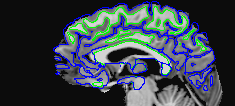

The following images show a T1 image with outlines for the outer boundary of gray matter (blue line) and white matter (green line).